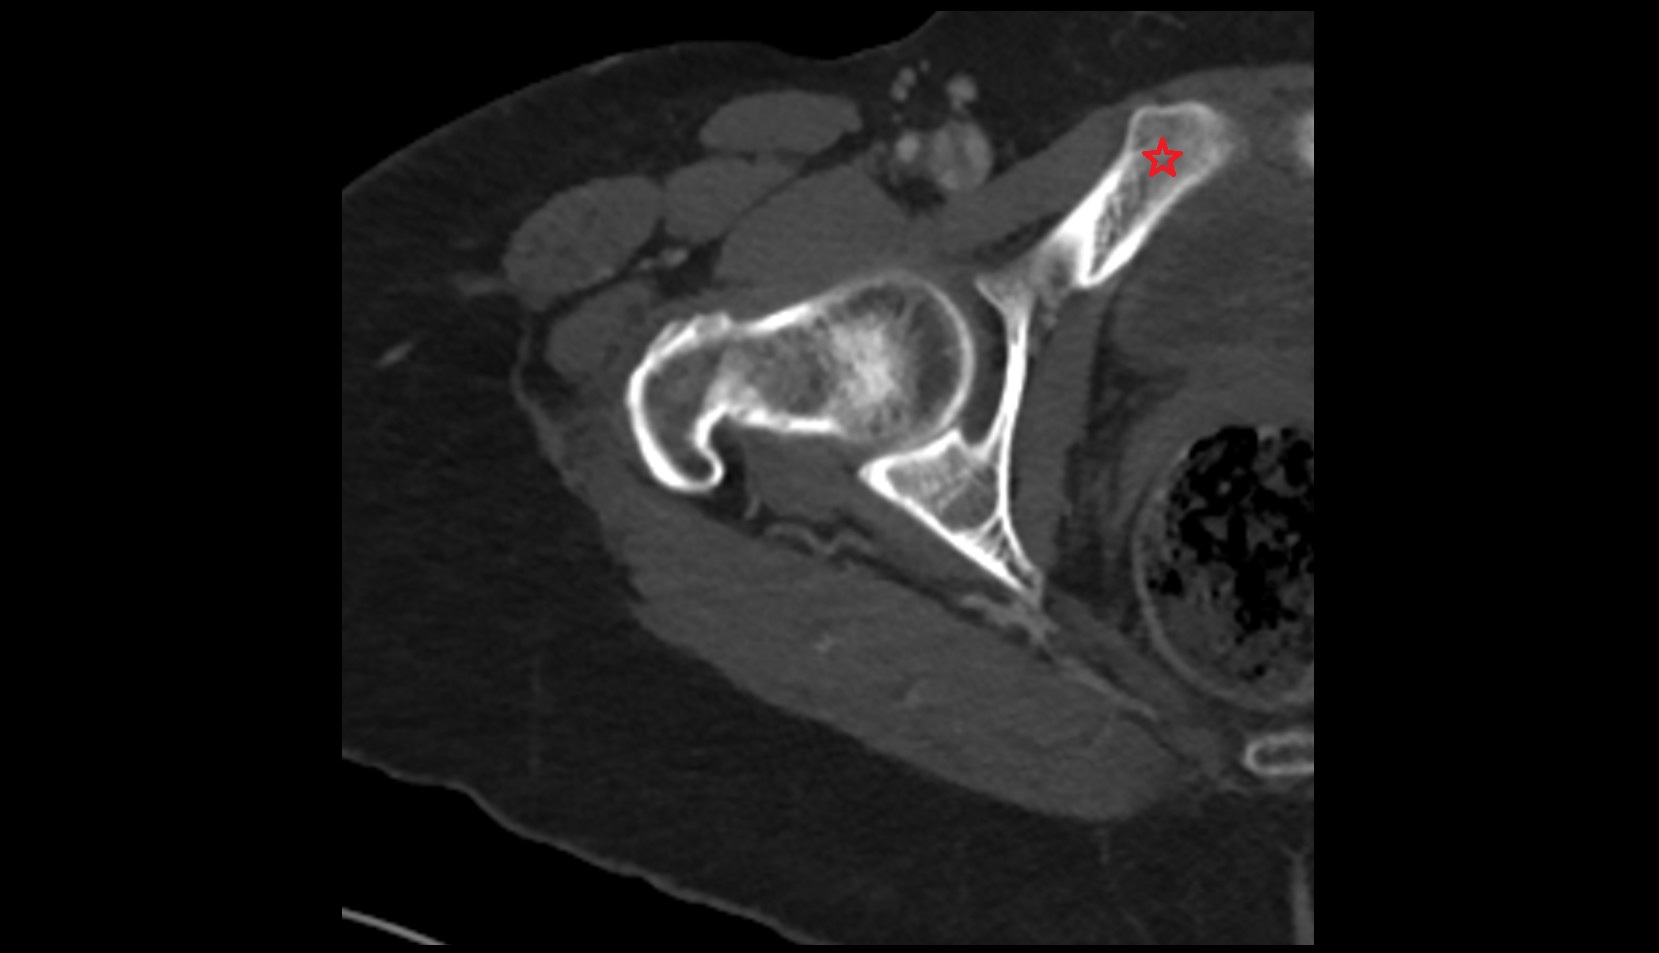

- Hip joint

- Acetabular margin (Acetabular rim)

- Acetabulum

- Head of femur

- Neck of femur

- Acetabular labrum